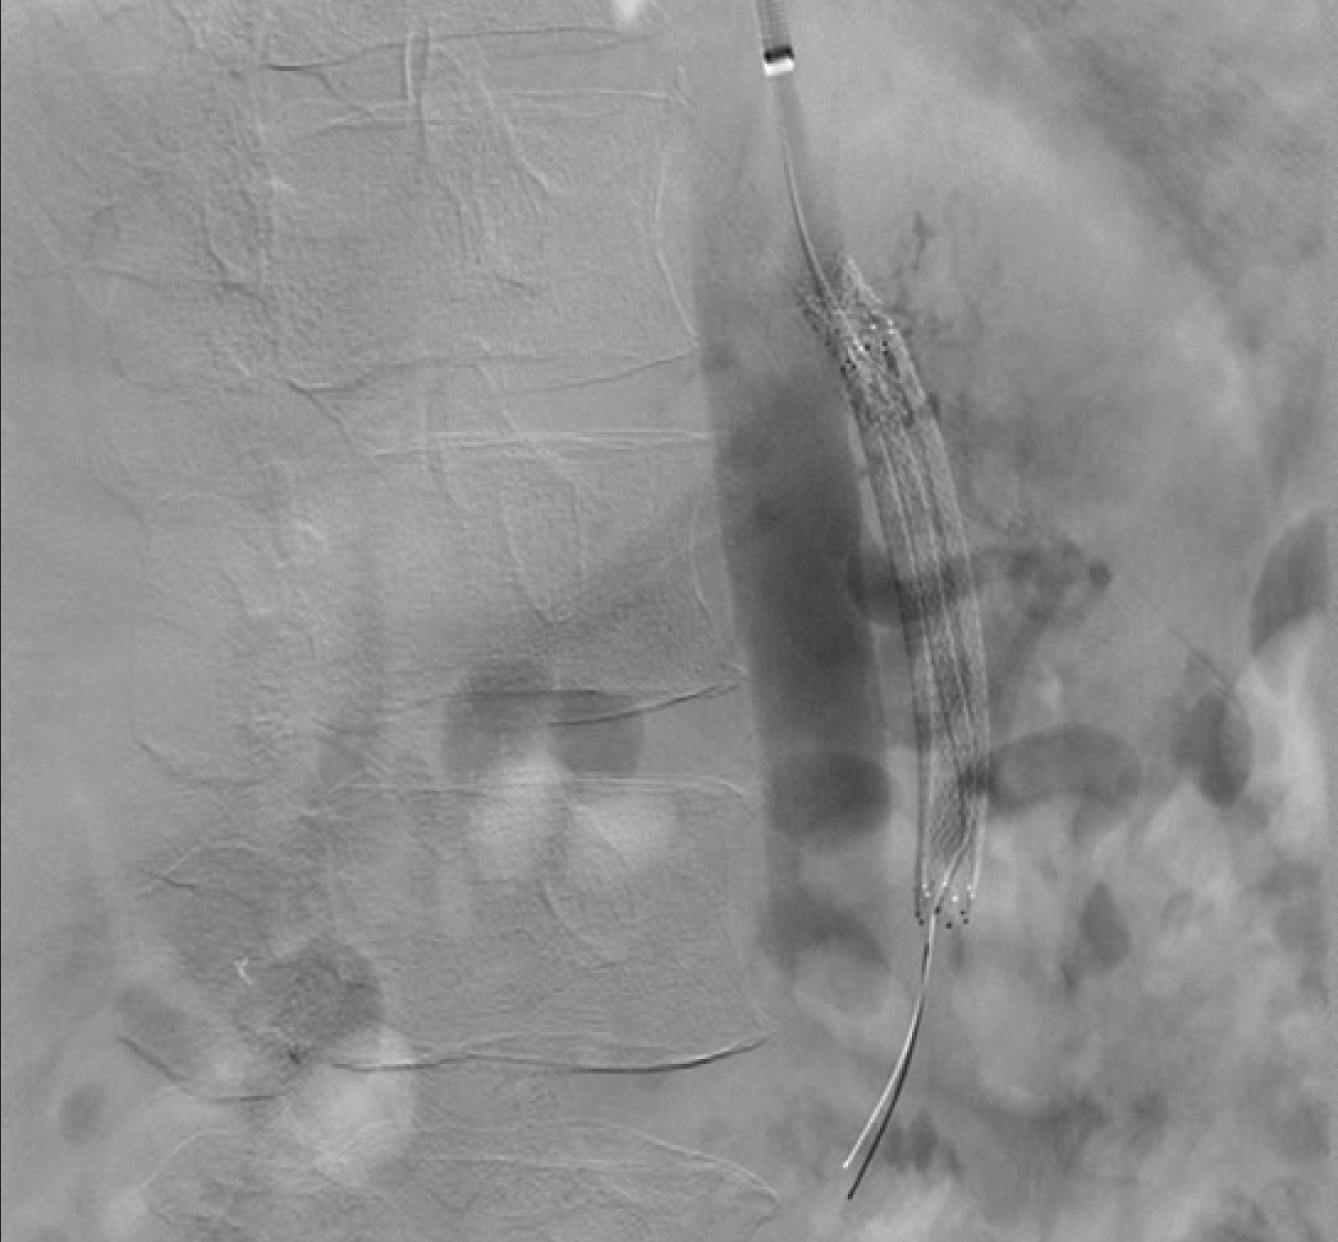

The procedure was performed under local anesthesia in a fully equipped hybrid operating room using fusion imaging guidance. Transfemoral selective catheterization and navigation of the upward-coursing, thrombosed aortorenal bypass was performed using a 7-F Penumbra Lightning Bolt catheter. CAVT with modulated aspiration restored flow through the bypass into the distal renal artery. Two stenotic lesions were identified on intraoperative angiography: one at the proximal aortograft anastomosis and another at the distal graft-to-native renal artery junction, which were treated concomitantly with a covered balloon-expandable stent and a covered self-expanding stent, respectively. Adjunctive local thrombolysis was performed with an intravascular bolus of 100,000 IU of urokinase, accompanied by temporary endoclamping of the bypass. Completion angiography confirmed successful revascularization of both the bypass and the target renal artery, with no residual stenosis and preserved renal parenchymal perfusion (Figure 3).

Figure 3. Completion angiography demonstrating patency of the left aortorenal bypass and distal renal artery, with preserved perfusion of the renal parenchyma.